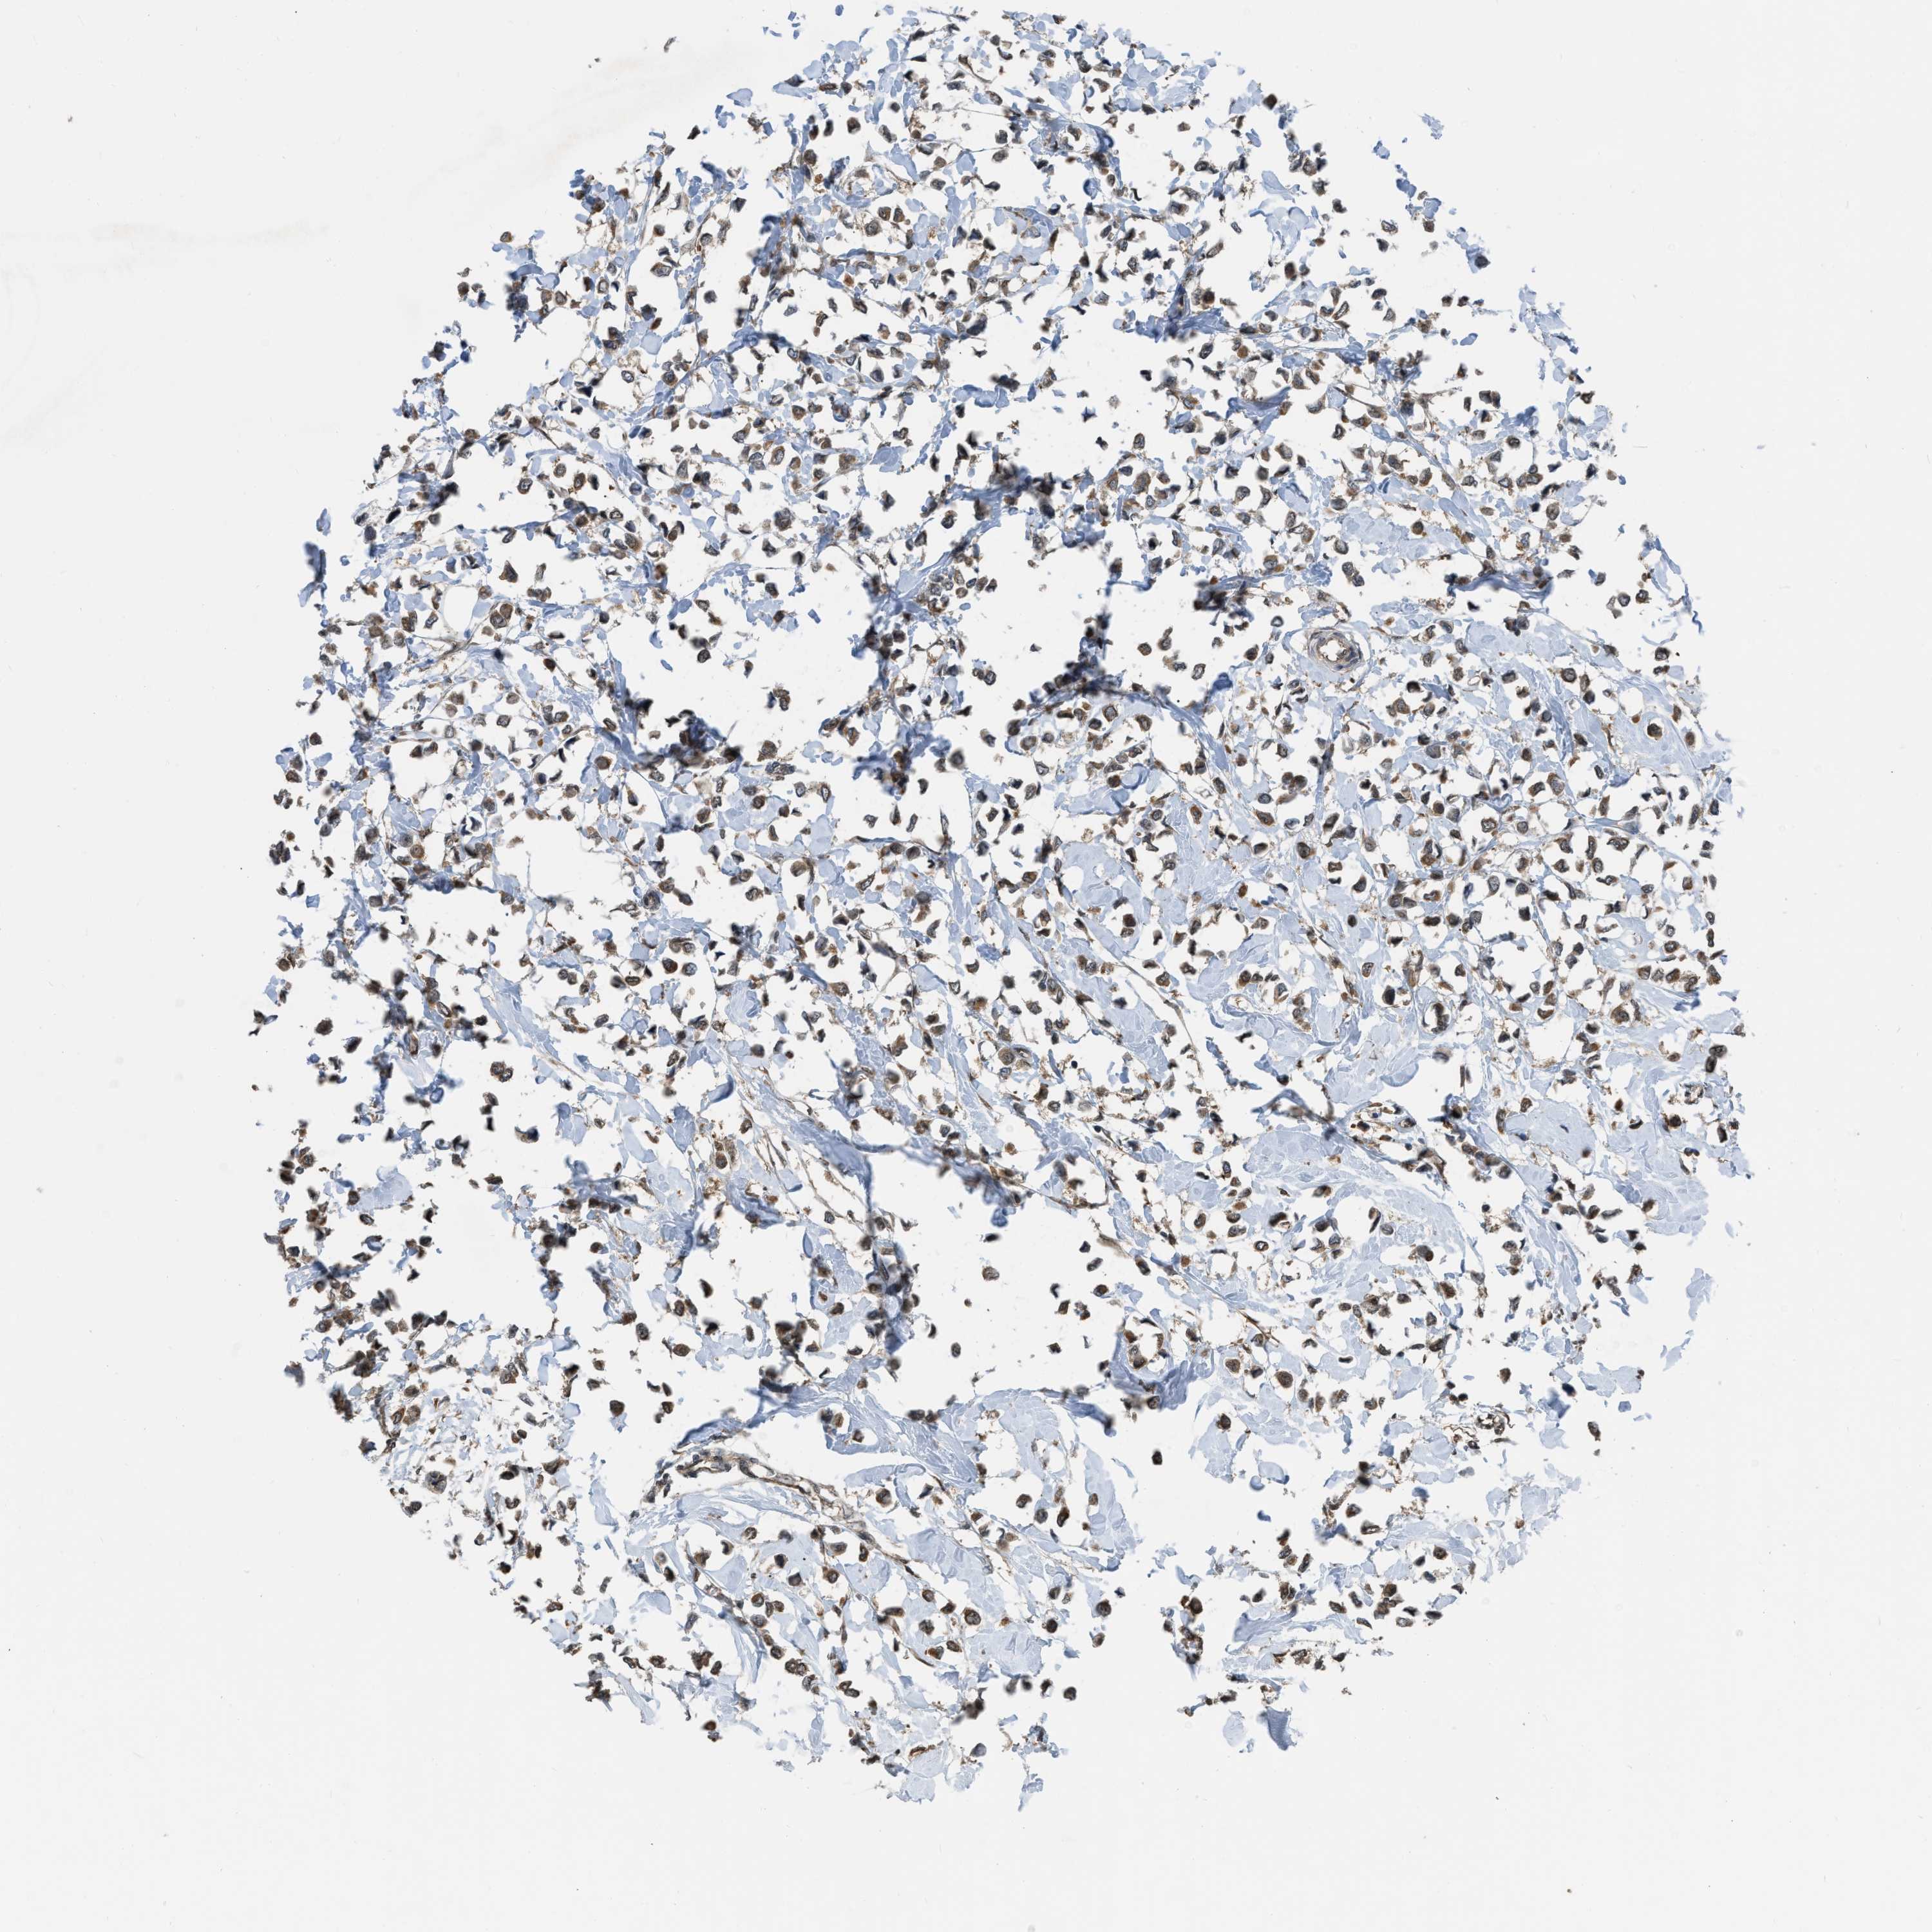

CANCER BREAST CANCER Show tissue menu

BRCA TCGA BRCA VALIDATION PROTEIN EXPRESSION